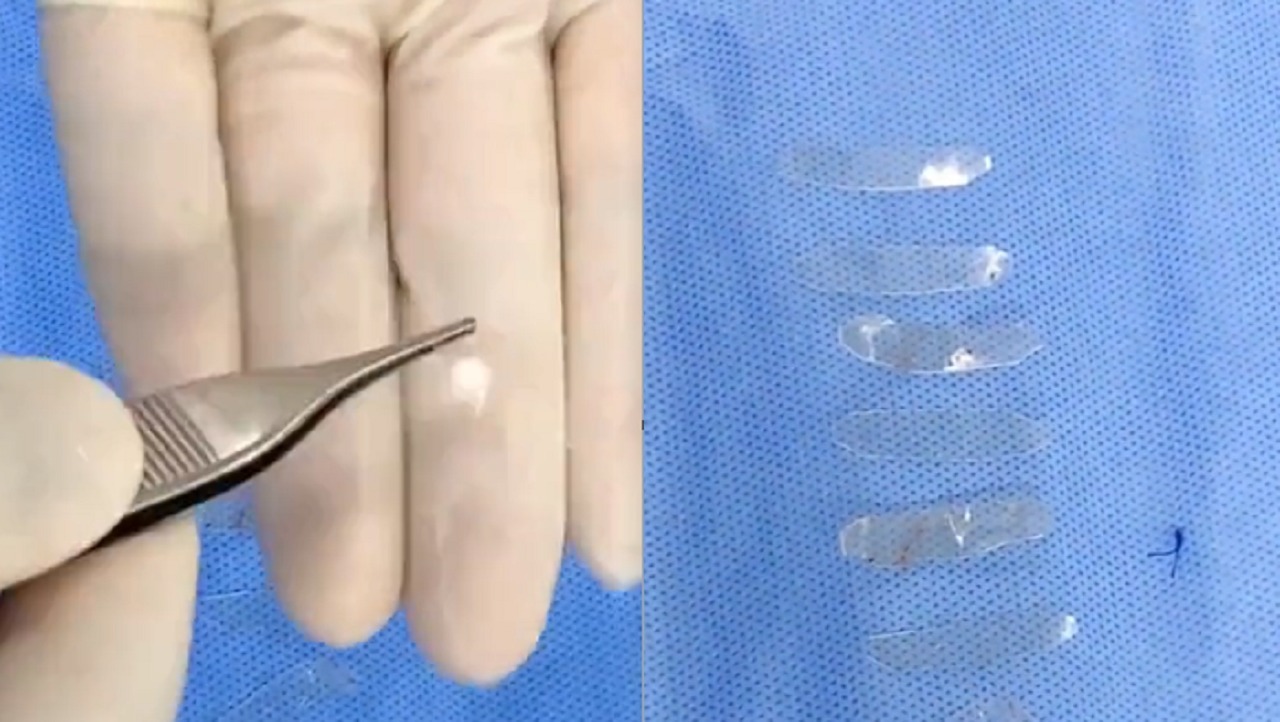

هذا ما وجده طبيب بأنف فتاة أجرت عملية تجميل منذ 7 سنوات..فيديو